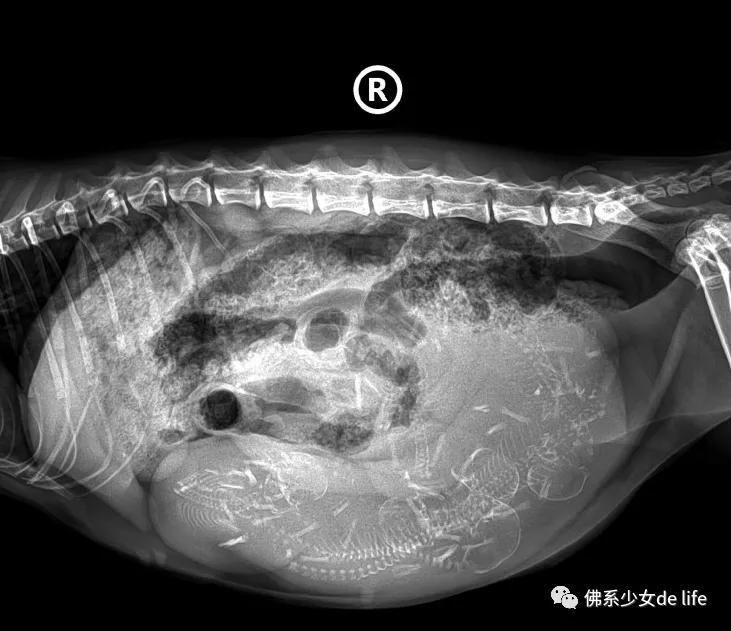

(配图是小编家“古丽”猫,宠物医院去产检时候拍的哈哈)

40+天就可以考虑拍两张X光啦,骨骼大多都比较清晰,有助于数个数,确定喵主怀了几只“小哪吒”,以免生完还要担心“肚子里还有?”同时打个B超看一下胎儿状态,个头明显变大,好动调皮的样子,初级爷爷奶奶美滋滋哈哈。

猜猜有几只小猫仔??